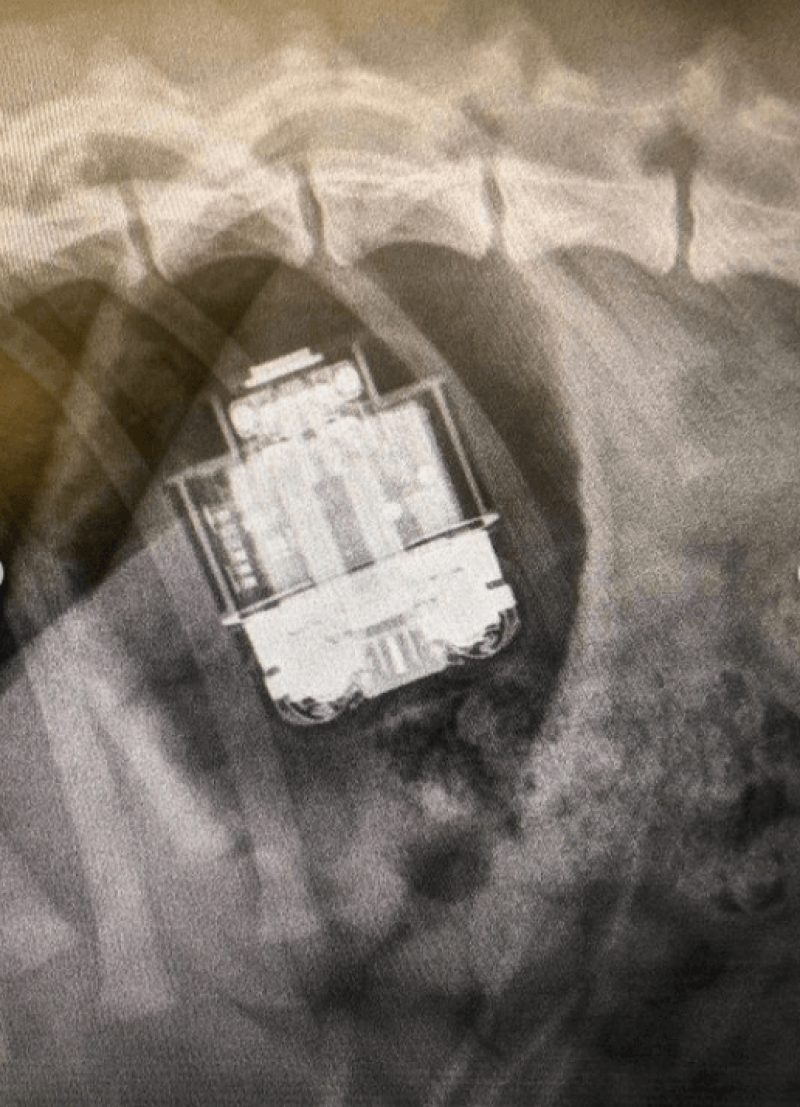

De AirPods zaten gelukkig nog in hun doosje, maar Rachel trok meteen naar een dierenarts waar Jimmy een operatie moest ondergaan. Aangezien het doosje de oortjes oplaadt, was er een reëel gevaar dat accuzuur in zijn maagje zou terechtkomen, zegt dierenarts Susana Jauregui. Tijdens de operatie werd duidelijk dat het doosje nog helemaal intact was: er zat geen enkele kras op en het lampje brandde zelfs nog.